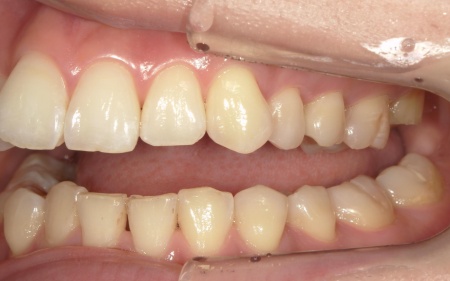

20代女性 前歯の歯並びをマウスピース矯正装置インビザラインGoで改善した症例

拝見したところ、叢生(そうせい)が上下前歯に確認できました。

今回のケースでは上前歯にやや目立つ重なりがあり、下前歯は軽度の叢生が見られました。

下あごの叢生は比較的軽度であり奥歯の噛み合わせにも問題がなかったこと、また上あごのみの治療にすることで費用面の負担も抑えられることから、今回は上あごのみの矯正治療を行う方針としています。